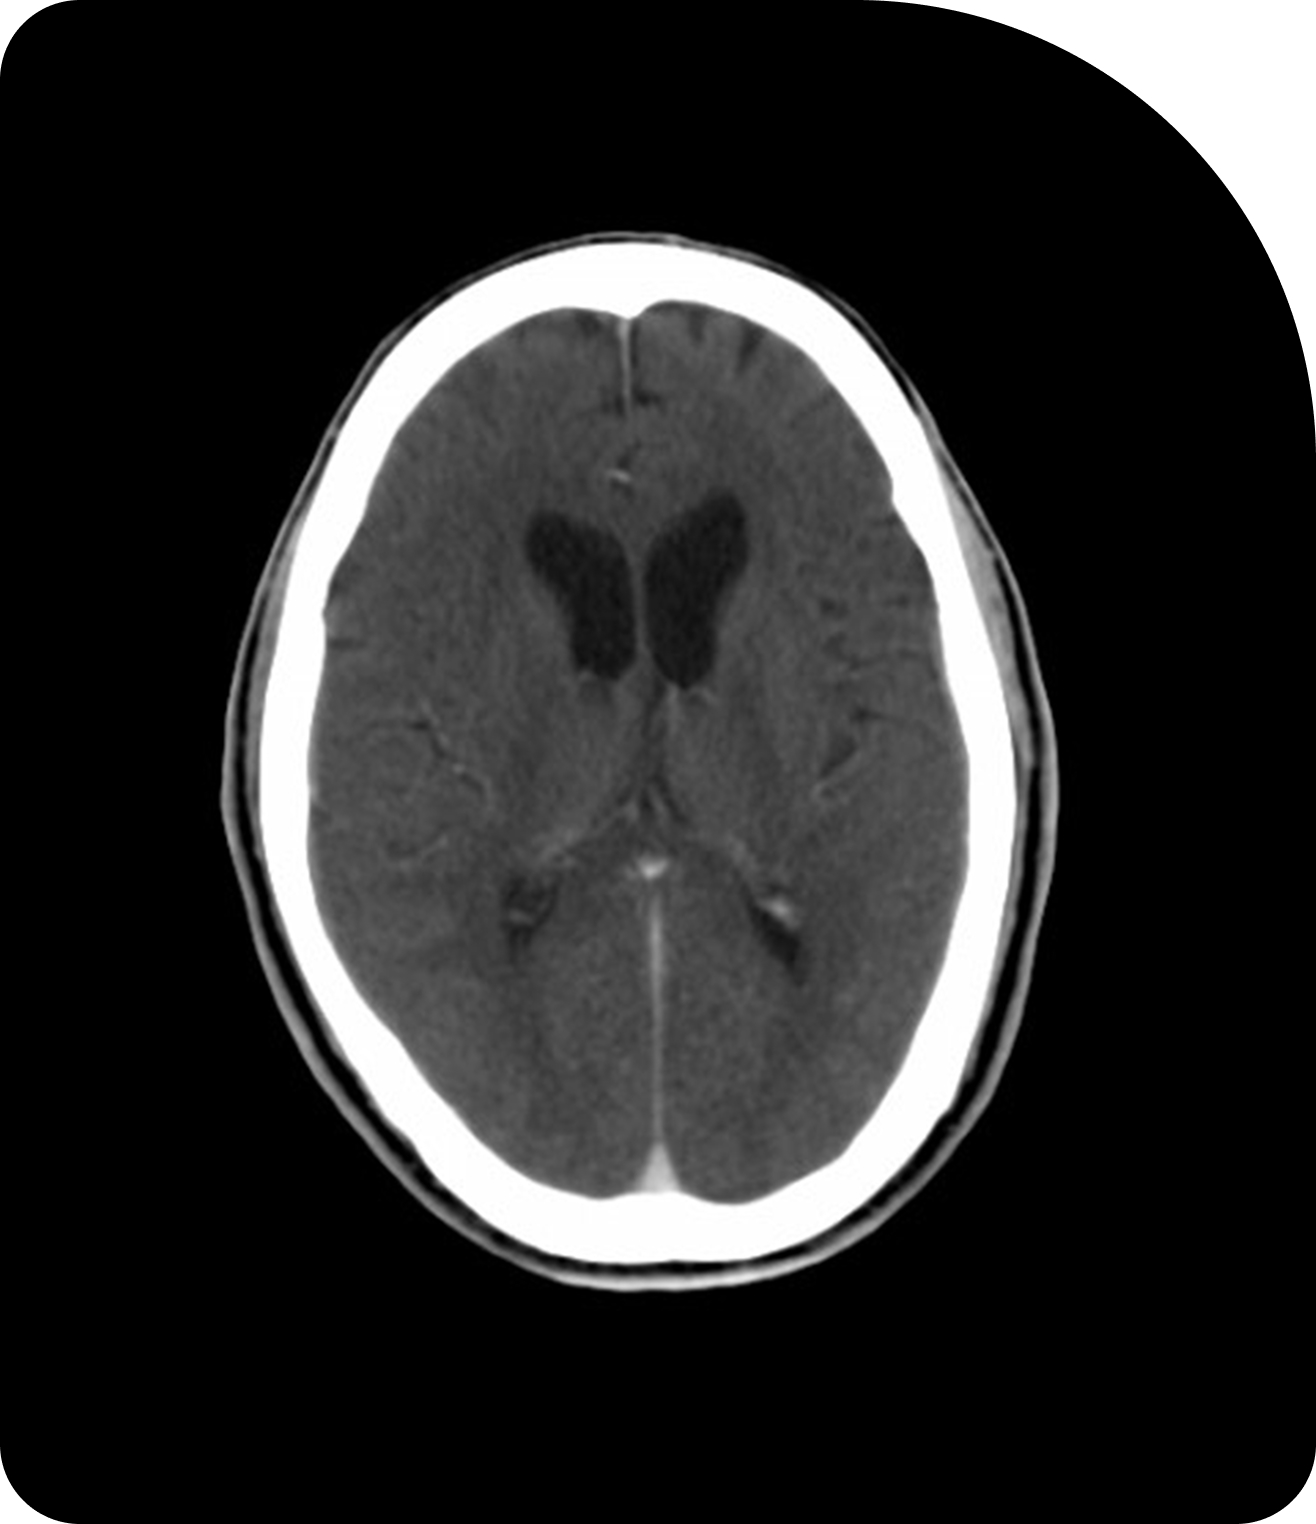

Clearer images mean more accurate targeting. Compare CT, CBCT, and MRI to see the difference.

CBCT

Cone Beam CT adds in-room imaging to support daily patient setup.

Widely used for daily imaging, CBCT provides three-dimensional visualization of the tumor and surrounding anatomy directly on the treatment machine. It helps detect positional shifts and anatomical changes before each session.